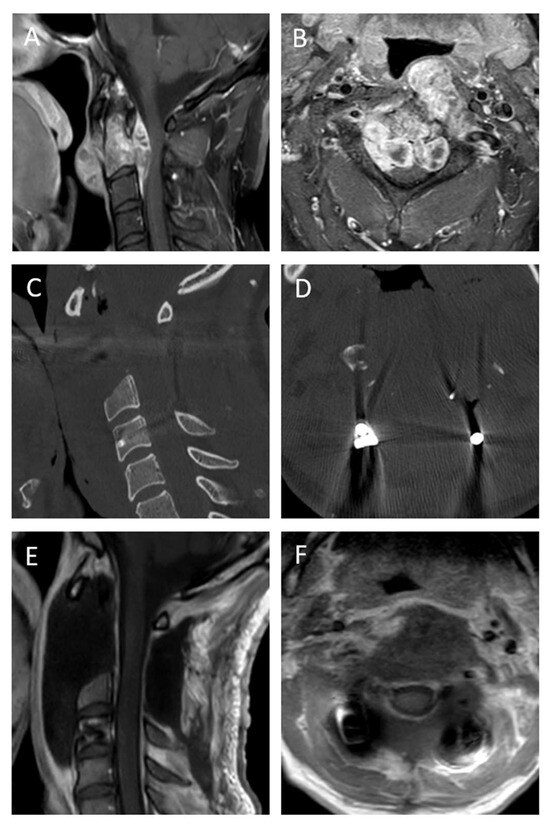

- A preoperative balloon occlusion test yielded negative results, indicating that occlusion of the vertebral artery was not tolerated, thus rendering an en bloc resection technically impossible.